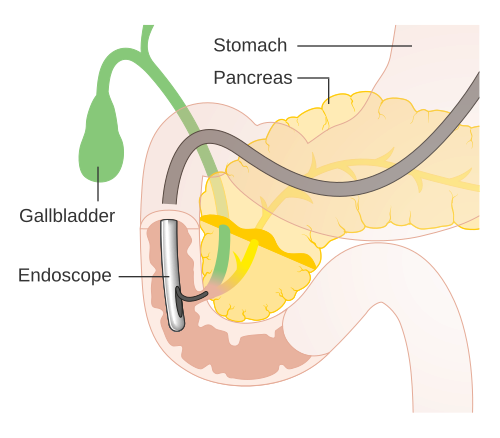

ERCP is a minimally invasive procedure. During this process, a thin flexible tube with a camera is passed through the mouth. It reaches the stomach and small intestine. This allows the doctor to see the bile duct clearly.

In addition, small tools can remove stones or open blocked ducts. Therefore, ERCP treatment in Bhopal helps both in diagnosis and treatment.

ERCP is not used for one problem only. Instead, it helps in managing several bile duct and pancreatic conditions.

Common conditions treated with ERCP treatment in Bhopal include:

- Bile duct stones

- Blocked bile duct

- Obstructive jaundice

- Pancreatic duct blockage

- Bile duct narrowing

Because these conditions may cause severe pain or infection, timely ERCP treatment becomes essential.